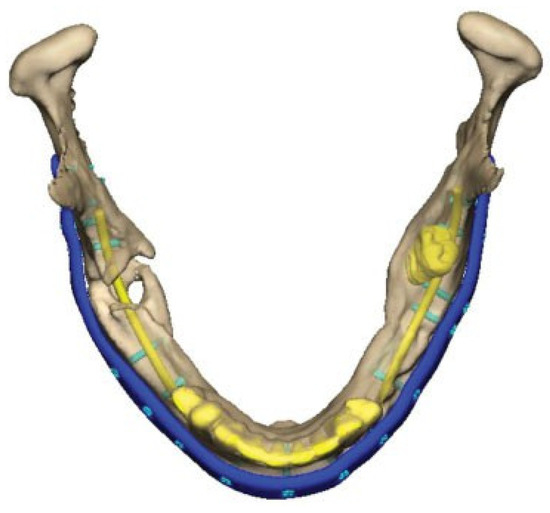

Figure 4.

After plate removal in the software, osteotomies in the fracture areas and corrective rotation of displaced fragments was performed to close the open bite and restore the occlusion in the virtual plan.

A Patient Specific Implant (PSI), an angle-to-angle mandibular reconstruction plate, was designed and outlined along the mandibular border. Plate holes with locking function for screws were outlined. The dimension of the plate was 2.5 mm thick and 8 mm wide. A total of 18 screw-holes were placed with care taken to avoid the fracture areas, teeth and nerves. (Figure 5) Simultaneously, a combined cutting- and drill guide was produced for osteotomies and drill holes virtually planned in the mandible. (Figure 6) The plate was then manufactured by milling from a titanium block (TRUMATCH® CMF, DePuy Synthes GmbH, Oberdorf, Switzerland) after the surgeon had approved its final form.

Figure 5.

Virtual design of plate and planning of holes and screw locations. Note the screws in the posterior left mandible avoiding the mandibular nerve and molar inside the bone.